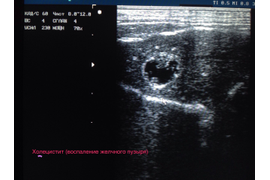

Ультразвуковое исследование в нашей клинике проводится на экспертном аппарате УЗИ Mindray Vetus 5.